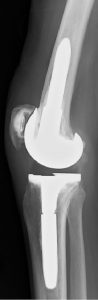

术前(左)和术后(右)关节X光图片病人三年来第一次外出手术

连续142名RA病历(201膝盖)从1997年8月22日到2011年3月16日拥有初级TKA所有程序均由单科外科医生在单一机构进行普通麻醉,所有病人都由同一名医生治病。79名病人口服类固醇,82名病人外科时服甲状腺素22名病人同时使用肿瘤消毒因子对立法处理TKATKA后,59名病人接受了生物治疗初级TKA后,106名病人单从膝部外科手术,其余36名病人额外接受低端联合外科手术,如全流节肢科全科全科全科全科节肢科全科全科全科全科全科全科全科全科全科全科全科全科全科全科全科全科全科全科全科全科全科全科全科全科全科全科全科全科全科全科全科全科全科全科全科全科全科全科全科全科全科全科全科全科全科全科全科全科全科全科全科全科全科全科全科全科全科全科全科全科全科全科全科全科全科全科全科全科全科全科全科全科全科全科全科全科全科全科全科全科全科全科全科全科全科全科全科全科全科全科全科提交者附属机构IRB(机构评审委)批准此项研究

Genesis2(Smith和Nephew,Memphis,TN,USA)在所有例子中都使用假肢类型,1997年8月首次提交115名病人(164个植入式)受难保留TKAs,25名病人(35个植入式)后稳定TKAs,2名病人修改TKAs(2个植入式)。术后第1天,所有案例都应用扩展膝盖支架,并开始ROM运动演练、连续被动运动和增强肌肉活动重生手术第二天允许使用,3周后开始爬楼梯开通T-Cane并忍受上行楼梯后,所有病人都出院

所有病人都评估成日本矫形协会评分(JOA评分)、活动ROM、X光检测结果、RA活动、户外振荡持续时间和移植累积生存率以百分位标度 JOA分数测量疼痛范围 手动肌肉测试 编译能力 爬楼梯能力疼痛标记40分 ROM标记12分 四叉肌肉强度标记20分 步行能力值20分 爬楼梯值8分JOA85或85以上评分被视为优异、70-84良好、60-69公平并低于60穷